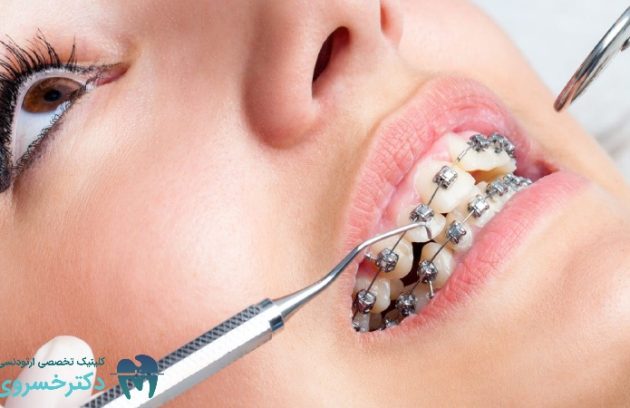

تشخیص ارتودنسی به صورت فردی

تشخیص ارتودنسی و اهمیت آن در درمان ناهنجاریهای دندانی